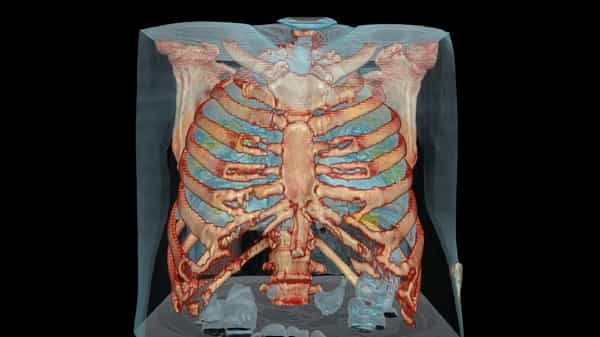

RIAUDETIL.COM – Dr Keith Mortman, seorang kepala bedah toraks di Rumah Sakit Universitas George Washington membagikan sebuah video virtual reality (VR) tentang dampak virus coronaCOVID-19terhadap paru-paru.

Dikutip dari CNN, video ini menggambarkan kerusakan paru-paru pada seorang pria berusia 59 tahun akibat infeksi virus corona di Amerika Serikat (AS). Pria tersebut diketahui awalnya tak bergejala sama sekali dan hanya memiliki riwayat hipertensi atau tekanan darah tinggi.

“Selain tekanan darah tinggi, dia tidak memiliki masalah medis yang signifikan. Ini adalah video sekitar seminggu lalu, kemungkinan infeksi dan proses peradangan bisa lebih buruk pada saat ini,” kata Mortman.

Area yang ditandai warna kuning pada video tersebut adalah bagian paru-paru yang terinfeksi dan meradang. Mortman mengatakan virus corona tak hanya menyerang pada beberapa sisi paru saja, melainkan mencakup hampir keseluruhan paru-paru.

“Umumnya pada pasien yang mengalami kegagalan pernapasan progresif, kerusakan pada paru-paru begitu cepat dan meluas,” ucap Mortman.

“Sayangnya begitu rusak seperti ini, butuh waktu yang cukup lama bagi paru-paru untuk bisa sembuh. Bahkan sekitar 2-4 persen dari pasien COVID-19 kerusakan pada paru-paru tidak bisa dipulihkan,” lanjutnya.

Menurutnya ketika virus corona menginfeksi, paru-paru akan bereaksi dengan cara melakukan peradangan sebagai mekanisme pertahanan.

Peradangan mencegah paru-paru mengisi darah dengan oksigen dan mengeluarkan karbon dioksida. Akibatnya yang dirasakan oleh pasien adalah seperti sesak napas.